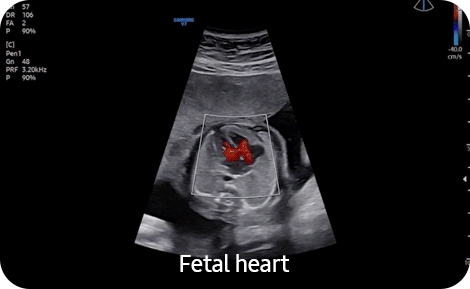

• 5D Heart Color- Модуль автоматического получения 9 стандартных плоскостей сердца плода из объемных данных STIC в соответствии с международными методическими рекомендациями с динамическим отображением кровотока 5D Heart Color. Необходим модуль 4D. (CV1-8AD, EV2-10A);

• MPI +- Модуль автоматического измерения миокардиального индекса MPI (индекса Tei) для оценки функции сердца плода (все внутриполостные датчики, CV1-8AD);